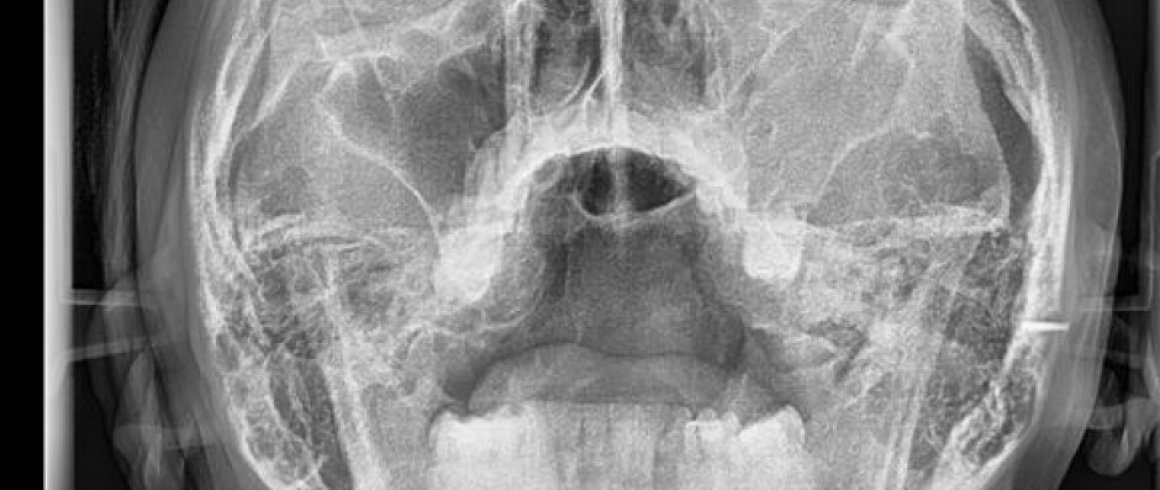

- Posteroanterior

- Análisis Cefalométrico Frontal